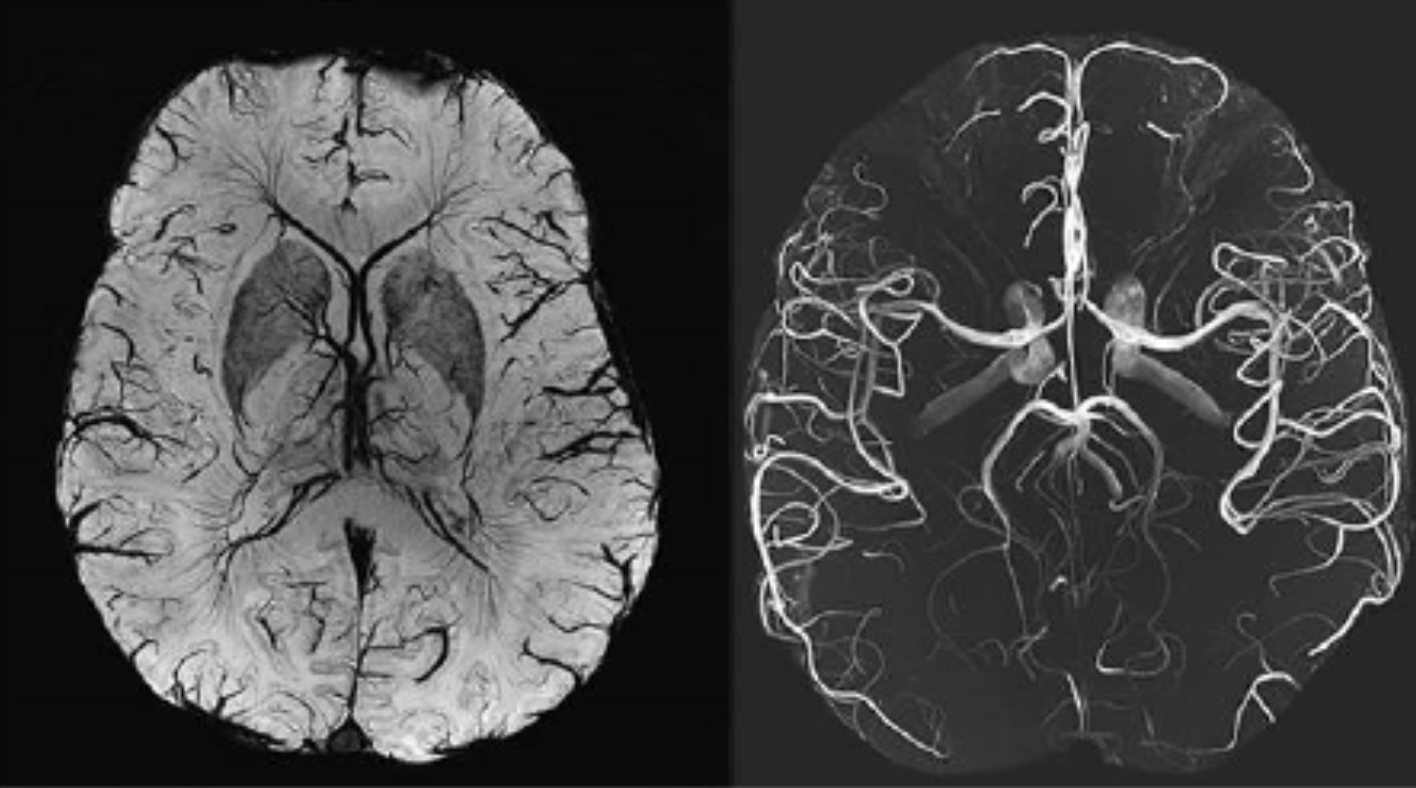

Alzheimer’s later in life likely comes from the decay of the blood-brain barrier, often from the blood vessel side. This used to be called white matter disease. Now we can see that it’s blood vessels.

This is thanks to powerful imaging technology – a massive 7-Tesla MRI machine, which can see small blood vessels in unprecedented detail. That’s how we can now see those vessels decay.